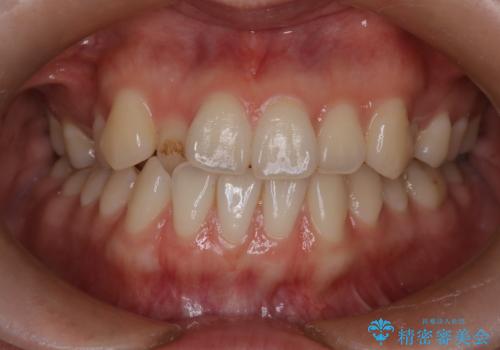

八重歯と前歯の逆の咬み合わせを、目立たない矯正で同時に改善

- 八重歯と、右上前歯(2番)が下の歯より内側に入っている反対咬合を気にされてご来院されました。精密な検査の結果、八重歯と反対咬合を同時に改善するためには、歯列全体にスペースを確保する必要があると判明。患者様のご希望から、透明で目立たないインビザライン(マウスピース矯正)による治療計画を立案しました。奥歯全体を奥へ動かす遠心移動でスペースを作り、これらの複雑な問題を一括で解消することを目指します。

今回の矯正治療では、透明なマウスピース型の装置インビザラインを使用しました。治療は、緻密なデジタル計画に基づき、奥歯から順に歯列全体を後方へ移動させる遠心移動を実施。これにより、八重歯を正しい位置に並べるためのスペースを確保しました。同時に、右上の2番を前方に誘導することで反対咬合を解消。結果として、抜歯することなく八重歯と反対咬合という複数の問題が改善され、機能的で美しい歯並びを獲得していただけました。